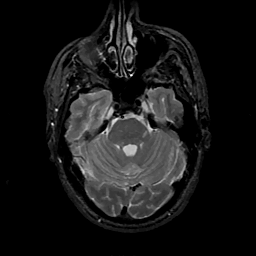

MR Study #11, May 5, 1991 -- Slice #14

[Home][Help][Clinical][Tour 1][Tour 2] Slice 14